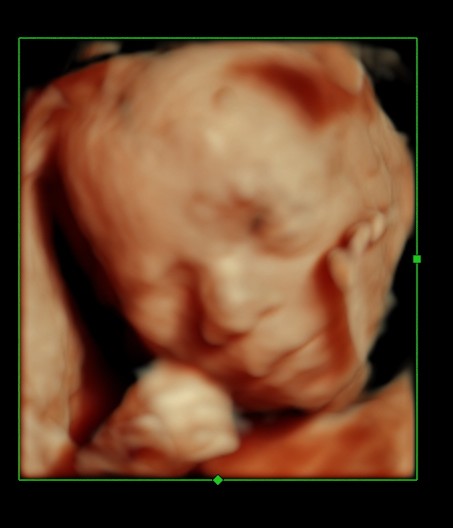

BABY FACE ( Just for fun ) Date: May 25, 2014Author: kriznan Category: 3 d images, fetal face, Fetal Ultrasound, ultrasound images Tags: baby face 3 d images, baby sucking finger, baby yawning Post navigation ← HEMANGIOMA OF THE LIVER IUGR OR SKELETAL DYSPLASIA OR RENAL DYSPLASIA → This is just an intermediate filler . enjoy the expressions. Thinking Yawning or just putting out the tongue Sucking the fingers Wondering So , what is lost now ? ok Papparazi ! enough for the day . go away. Share this: Share on X (Opens in new window) X Share on Facebook (Opens in new window) Facebook Email a link to a friend (Opens in new window) Email Share on LinkedIn (Opens in new window) LinkedIn Share on WhatsApp (Opens in new window) WhatsApp More Print (Opens in new window) Print Share on Reddit (Opens in new window) Reddit Share on Tumblr (Opens in new window) Tumblr Share on Pinterest (Opens in new window) Pinterest Share on Telegram (Opens in new window) Telegram Like Loading...